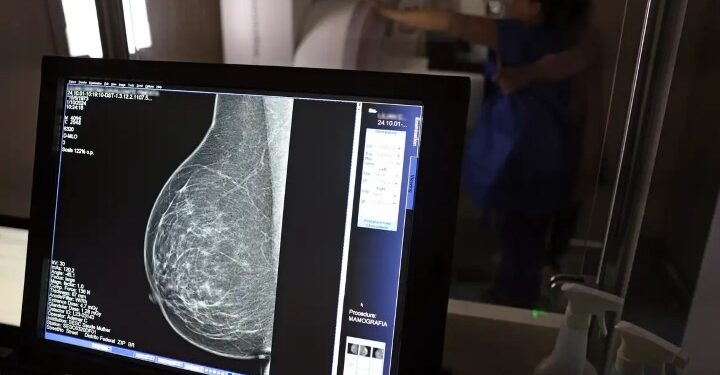

Brasília – A Advocacia-Geral da União (AGU) entrou com uma ação civil pública contra o médico Lucas Ferreira Mattos por disseminação de desinformação sobre a mamografia. O profissional afirmou, em postagens nas redes sociais, que o exame poderia causar câncer de mama, declaração que vai contra as evidências científicas.

A declaração motivou investigações por parte dos Conselhos Regionais de Medicina de Minas Gerais e São Paulo. O Instituto Nacional do Câncer (Inca) também se manifestou, esclarecendo que não há evidências de que a mamografia cause câncer e ressaltando que o exame é essencial para a prevenção e detecção precoce da doença.

Em nota, a AGU afirmou que “a propagação de desinformação sobre o tema pode desestimular mulheres a realizarem o exame preventivo, comprometendo as políticas públicas de enfrentamento ao câncer de mama”. O órgão anexou ao processo uma nota técnica do Ministério da Saúde que recomenda que mulheres entre 50 e 69 anos realizem mamografias de rastreamento a cada dois anos para detectar precocemente a doença.